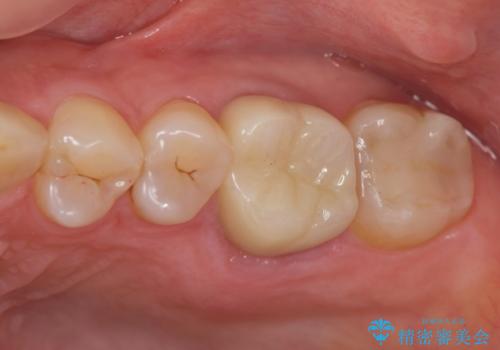

- 銀歯が取れたのち放置してしまいセラミック治療を希望され来院されました。

虫歯の再発も見られたので、丁寧に虫歯を取り除いたのち根管治療を行いジルコニアクラウン・セラミックインレーにより修復処置を行いました。

- 19.8万円(仮歯・ジルコニアクラウン・セラミックインレー)費用は治療当時の料金となります